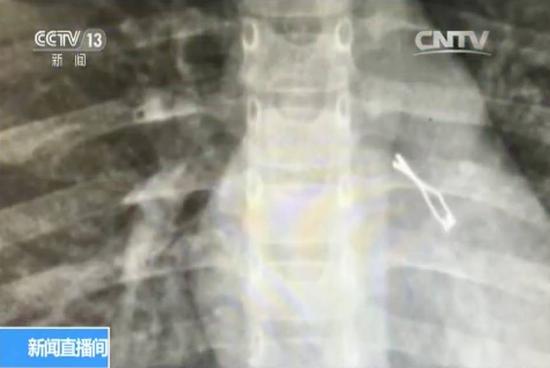

从彤彤的胸部X光片中可以看到,她的左肺里有一个类似于发夹形状的金属制品,而且吸入气管非常深。医生表示,由于灯泡边缘很锋利,取出来难度不小,很容易划伤气管,引起大出血。

X光片